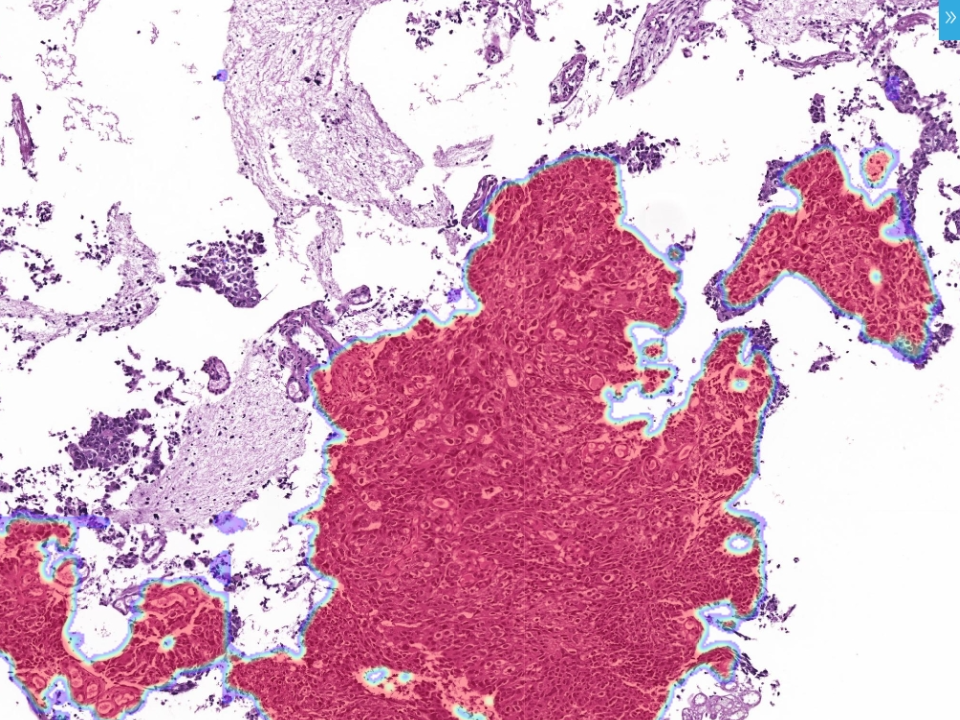

Hydrothorax and Ascites Cytology Assistant Diagnostic Module

Automatic recognition of malignant tumor cell Assist physicians with cytologic diagnosis. Whole slide analysis to reduce misdiagnosis.. Validated by multi-center clinical trials: sensitivity≥96%,specificity≥90%, Quantities 10000+ Increase the positive detection rate

Hydrothorax and Ascites Cytology Assistant Diagnostic Module

Automatic recognition of malignant tumor cell Assist physicians with cytologic diagnosis.

Whole slide analysis to reduce misdiagnosis..

Validated by multi-center clinical trials: sensitivity≥96%,specificity≥90%, Quantities 10000+

Increase the positive detection rate